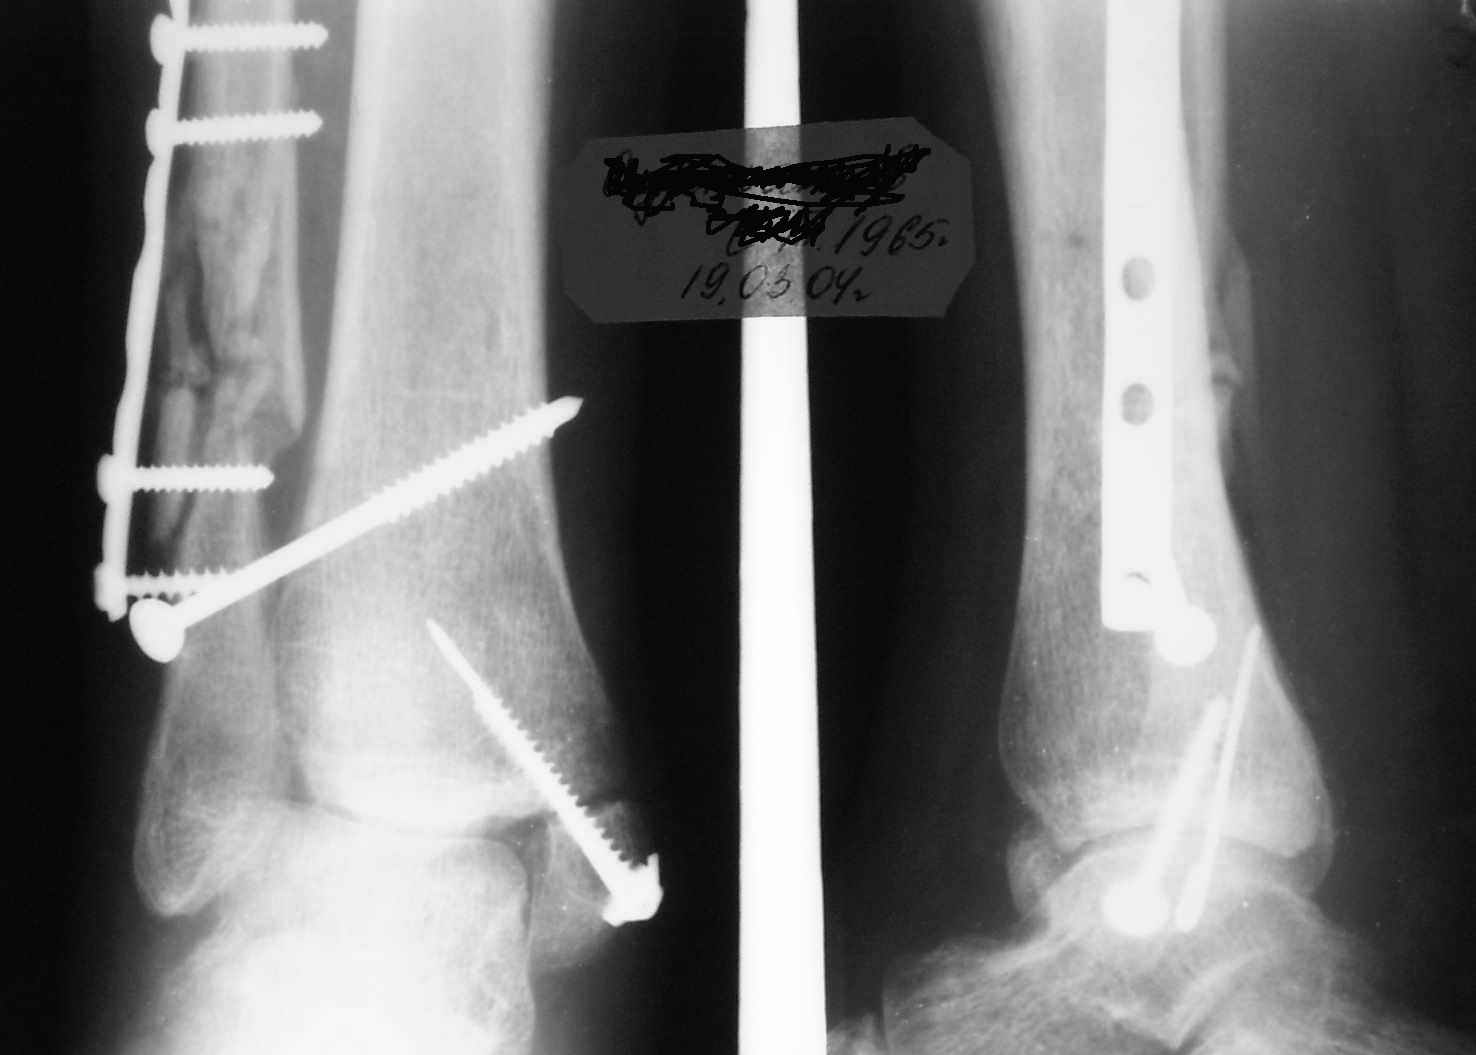

С подобным случаем приходилось сталкиваться у гормонозависимого пациента с 4 месячным подобным переломом после безуспешного лечения в аппарате Илизарова. Вальгусная стопа, остеопороз, диастаз в медиальной лодыжке. Произвел открытую репозицию мед лодыжки, синтез тяговым винтом 3.5 мм из титана, костную пластику спонгиозой, до 2 см куб из надлодыжечной зоны. Затем остеотомия по линии перелома малоберцовой кости узким долотом из 0.5 см доступа и ручная коррекция вальгуса . Блокирующий винт через обе кости. Остеосинтез по MIPO технологии пластиной 1-3 трубки. Внешней фиксации не применялось, перелом сросся за три месяца. Согласен с д-ром Кульжановым, без пластины в подобных случаях не обойтись.